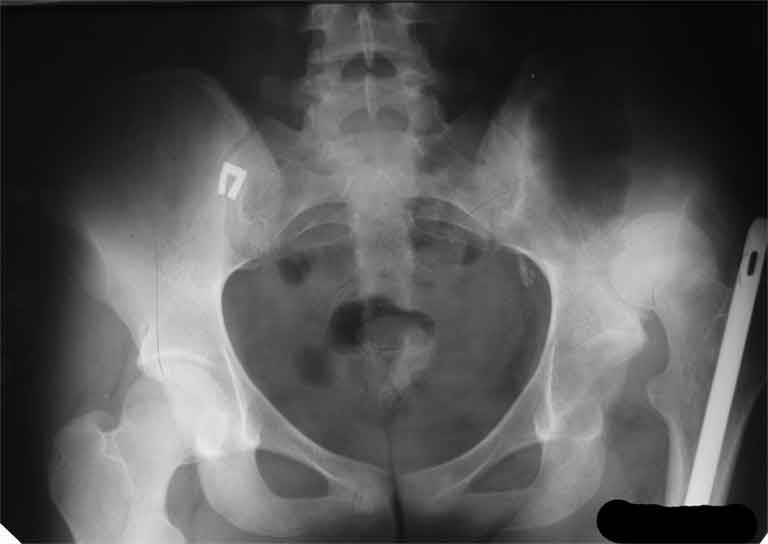

А нельзя показать снимок таза с контралатеральным суставом.

> А нельзя показать снимок таза с контралатеральным суставом.

А за счет чего такое укорочение? По снимку не видно соответствующего дефекта. Ну плюс приводящая контрактура - но все равно как-то уж больно много. Может, сделать снимки и таза обзорный с обоими проксимальными отделами бедра, и коенный суставов с приложенной линейкой какой?

Невозможно не согласиться с Анатолием, чтобы заниматься адекватным планированием как минимум прямая проекция таза должна быть сделана, как

максимум для оценки состояния мышц( насколько реально возможно низвести бедро) прямая проекция таза с тракцией за больную ногу.

I agree with Dr Eid's comments. The origin of the 8 cm leg length difference is a puzzle. Is this a clinical measurement? In that case contracture of the joint might affect the measurement. Can we see an AP pelvis to include both hip joints (including a calibration object with a known length) so that the difference in leg lengths that can be ascribed to the hip deformity and bony reabsorption can be measured. This sort of xray will help with templating for the TJR also. I would be very tempted to do a one stage procedure and accept some shortening. Shoe lifts should take care of a 3-4 cm difference.

Congratulations. Later on, could you post a true AP view of the pelvis and both hips?